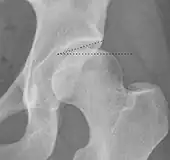

Projectional radiography ("X-ray")is often considered first line for FAI.[10] Anterior-posterior pelvis and a lateral image of the hip in question should be attained.[10] A 45-degree Dunn view is also recommended.[10][19]

| Femoral head-neck offset | ![]() |

Offset of the femoral head with regard to most prominent aspect of the femora neck | >10 mm |